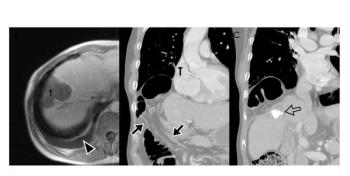

Though generally deemed safe, high-intensity focused-ultrasound ablation of liver and pancreas cancers can lead to delayed complications. According to Korean researchers, practitioners should be aware of-and watch closely for-local and systemic post-HIFU side effects several years down the road.